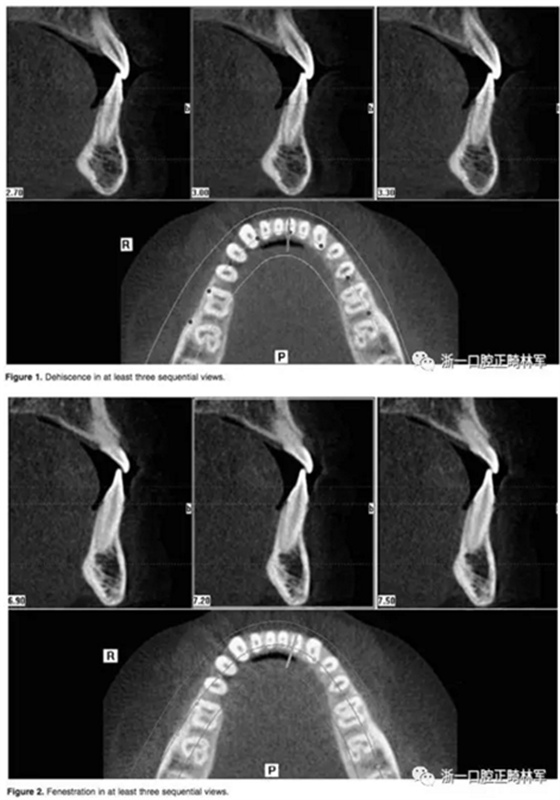

在iCAT配套軟件上進(jìn)行數(shù)據(jù)的二次三維重建。這種二次重建能夠創(chuàng)建最大精度的三維圖像使我們能夠進(jìn)行線性測(cè)量。每根牙根在軸向和橫斷面的切片上進(jìn)行距離頰舌側(cè)牙槽骨距離的評(píng)估。在至少三個(gè)連續(xù)的視圖中,牙根周圍沒有皮質(zhì)骨的情況被認(rèn)為是牙根周圍存在牙槽骨缺損。如果牙槽骨高度低于釉牙骨質(zhì)界超過2毫米,記為骨開裂。如果牙槽骨的缺損位于牙槽嵴下方而未至牙槽嵴頂,記為骨開窗。